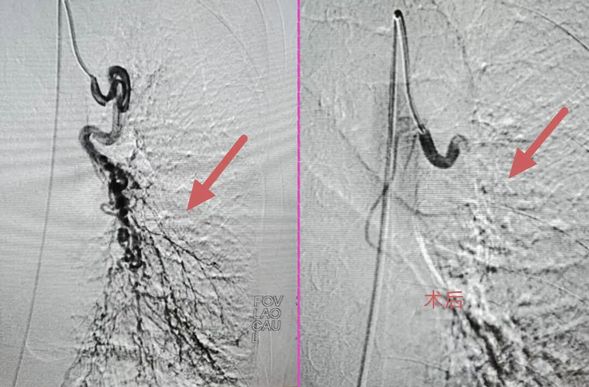

术前术后对比影像

我院介入科负责人莫庆国带领核心团队火速到场,结合患者肺癌病史与支气管扩张基础疾病,快速明确诊断为肺癌侵犯支气管动脉引发的急性大咯血,判定常规止血治疗无效,需立即实施介入栓塞手术封堵出血血管。我院介入科负责人莫庆国凭借二十余年临床经验,成功将栓塞材料精准送至出血靶点并完成封堵。患者术后转入ICU接受密切监护,次日生命体征稳定后转回介入病房。